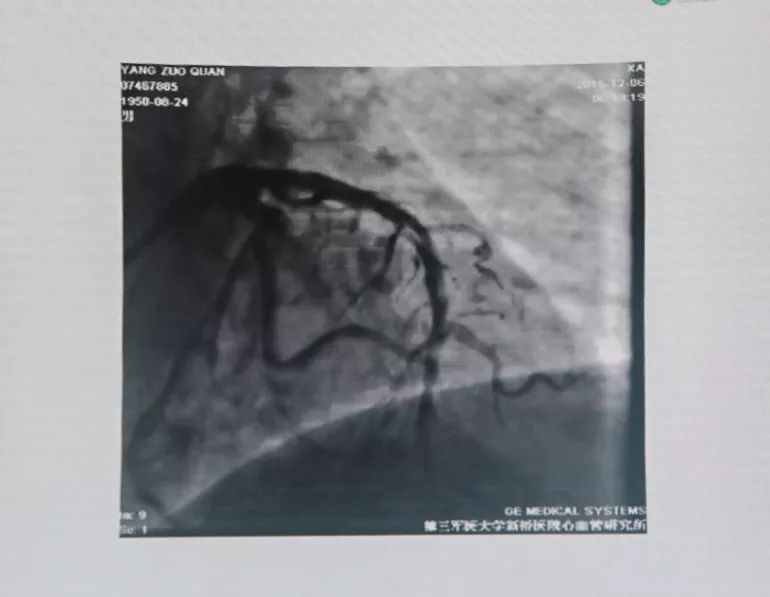

联系陆军军医大学第二附属医院胸痛中心,考虑亚急性支架内血栓形成,绕行急诊,PPCI。

有条件者应尽快进入导管室行急诊冠状动脉造影,以多体位投照明确无夹层及支架膨胀不良。若血管完全闭塞,待球囊扩张部分血流恢复后再行造影。应尽快使导丝通过血栓病变,建议应用软头导引导丝。

支架内血栓形成可能与支架未充分贴壁有关。可用短于支架长度的高压球囊再次PTCA。若造影确认血栓形成可能与支架近或远端内膜撕裂、支架未完全覆盖病变有关,可再次置入支架,视察20 min后,若患者胸痛缓解、血压及心电监测稳定、TIMI血流III级,可视为成功。但应关注,除非有证据显示血栓形成与上述因素相关,否则不可再次置入新支架。Dutch研究发现,首次出现支架血栓的患者,再次置入新支架,发生支架血栓的风险比未置入新支架的患者增加4.2倍。